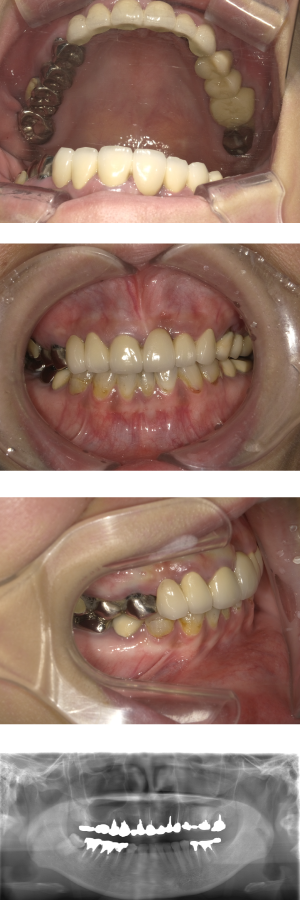

30代 女性 奥歯 インプラント

| 年代・性別 | 30代・女性 |

| 治療回数 | 10回(術前治療・検査除く) |

| 治療期間 | 約1年 |

| 料金 | ¥410,300(税込)※別途検査料 |

失った歯を補うために、インプラント治療は優れた治療方法です。 しかし、全ての人にインプラント治療が優れている治療ではありません。 |

| 副作用 | 術後に腫れ・痛みが出る可能性がある。 |